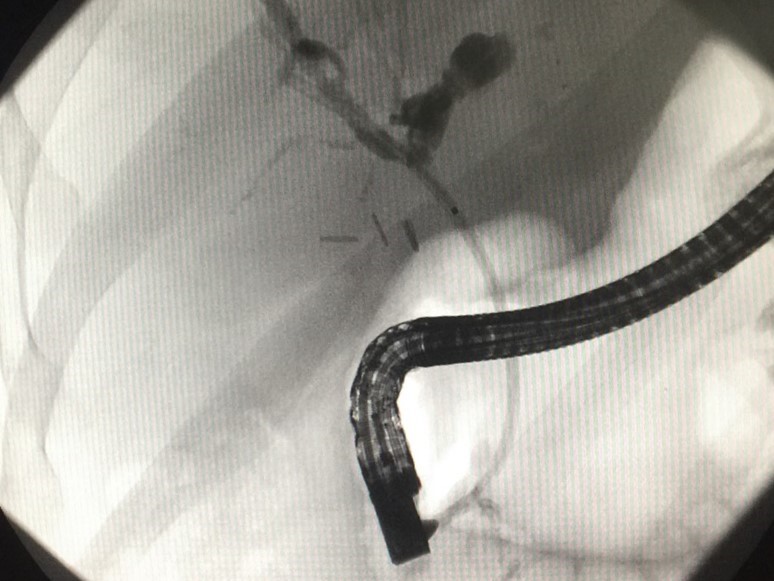

Recent echipa de endochirurgi formată din Cotoneţ Alic şi Bodrug Roman a realizat una din cele mai dificile protezări ale ductului hepatic comun cu proteza metalică autoexpandabilă. Un caz depăşit de neoplasm perihilar hepatic, la care mai multe tentative endoscopice şi intervenţii chirurgicale tradiţionale au eşuat. Anterior, la prima şedinţă endoscopică s-a reuşit canalizarea ductului hepatic comun şi instalarea unei proteze biliare din palstic. Starea pacientului s-a ameliorat, iar după două cure de chimioterapie la o adoua intervenţie endoscopică, proteza din plastic a fost înlocuită cu una metalică autoexpandabilă. Astfel de proteze asigură un flux biliar adecvat pe o perioadă de timp mai îndelungată.